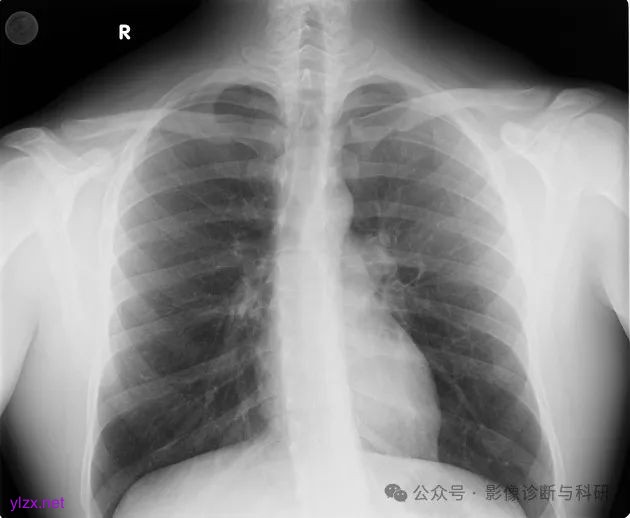

双侧锁骨胸骨端下表面有明显的菱形窝(凹陷型)

双侧菱形窝凹陷

双侧菱形窝凹陷,右侧为著